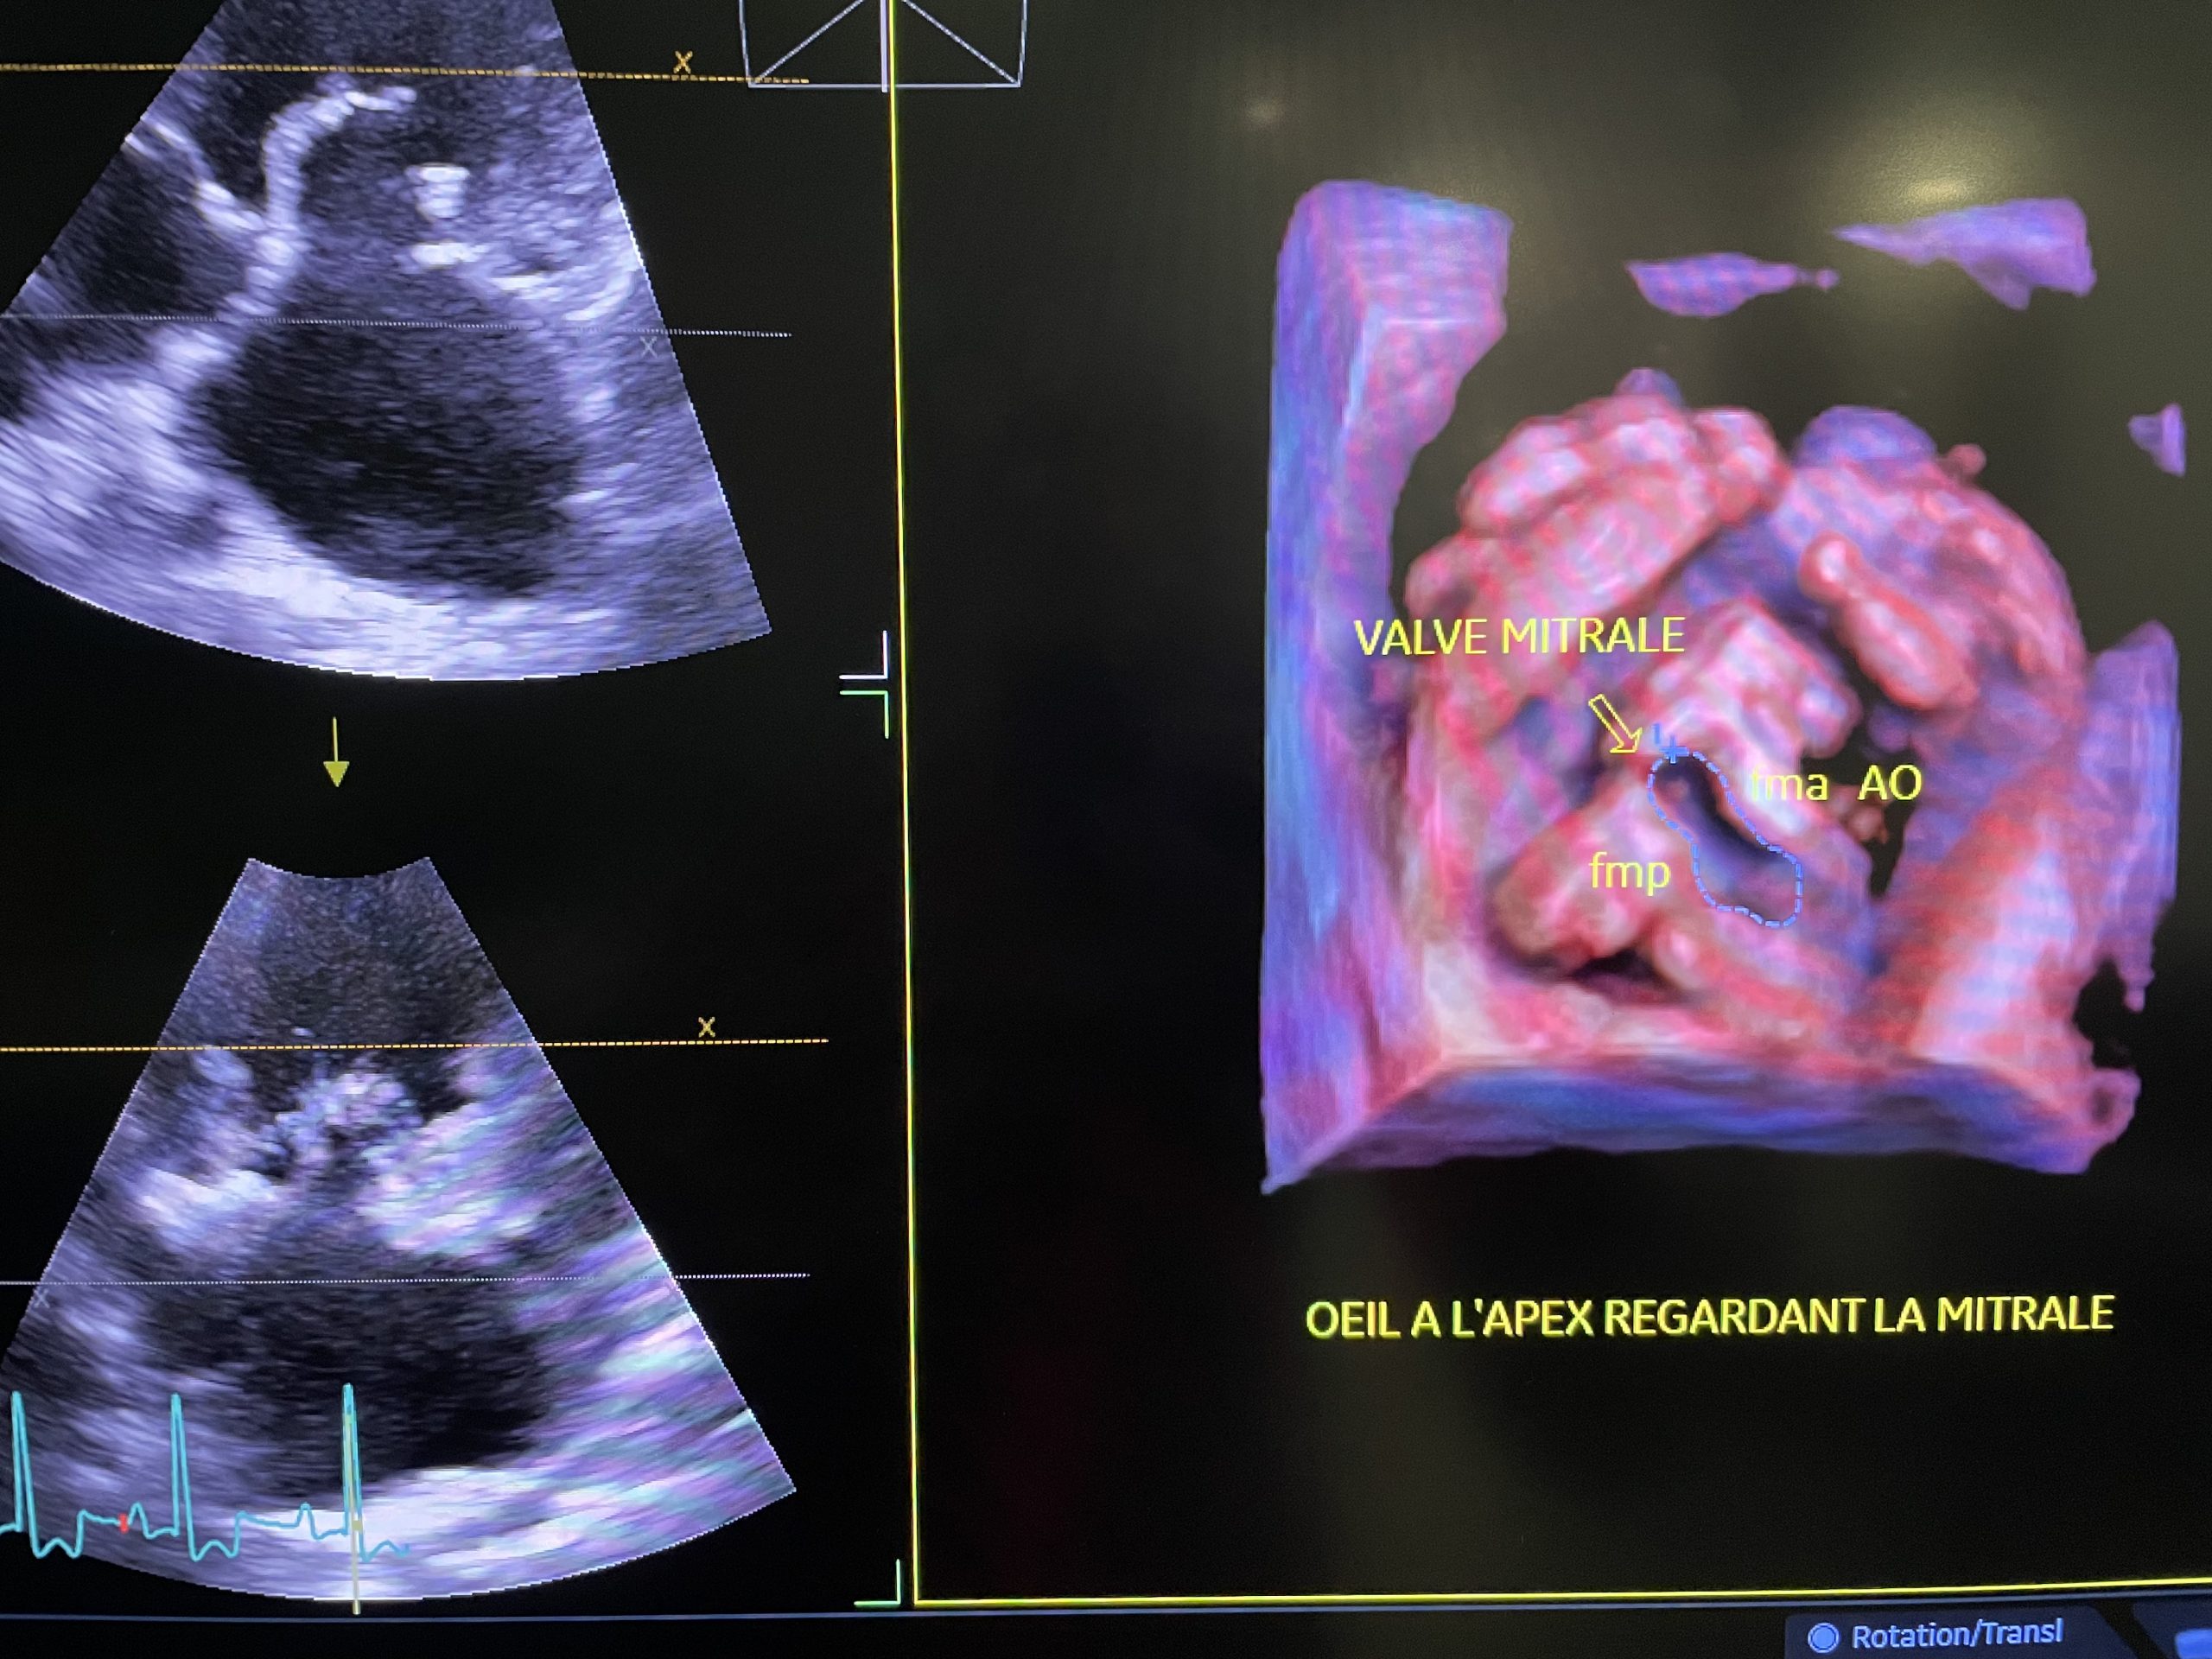

- Échodoppler cardiaque transthoracique (ETT) 2D et 4D

- Échodoppler cardiaque transœsophagien (ETO) 2D et 4D

2 Échographes 4D GE Vivid E95 (2016 et 2021)

2 Sondes Transoesophagiennes 2D & 4D GE (2016 et 2023)

- Maladie valvulaire dégénérative mitrale